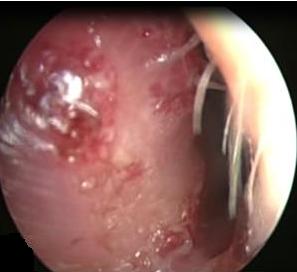

It is an autosomal dominant vascular disorder, which has a variety of clinical manifestations, with epistaxis being one of the most common. Many treatment options exist for epistaxis, but with no consensus on which is the method of choice. We describe the case of a patient with hereditary hemorrhagic telangiectasia (HHT) secondary epistaxis with septoplasty managed with synthetic hard graft, which improved intensity and frequency of bleeding episodes. This technique is a variant of the septodermoplasty described by several authors, but the use of synthetic dura can help in obtaining better results and avoid taking skin grafts from other sites different from the surgical site.